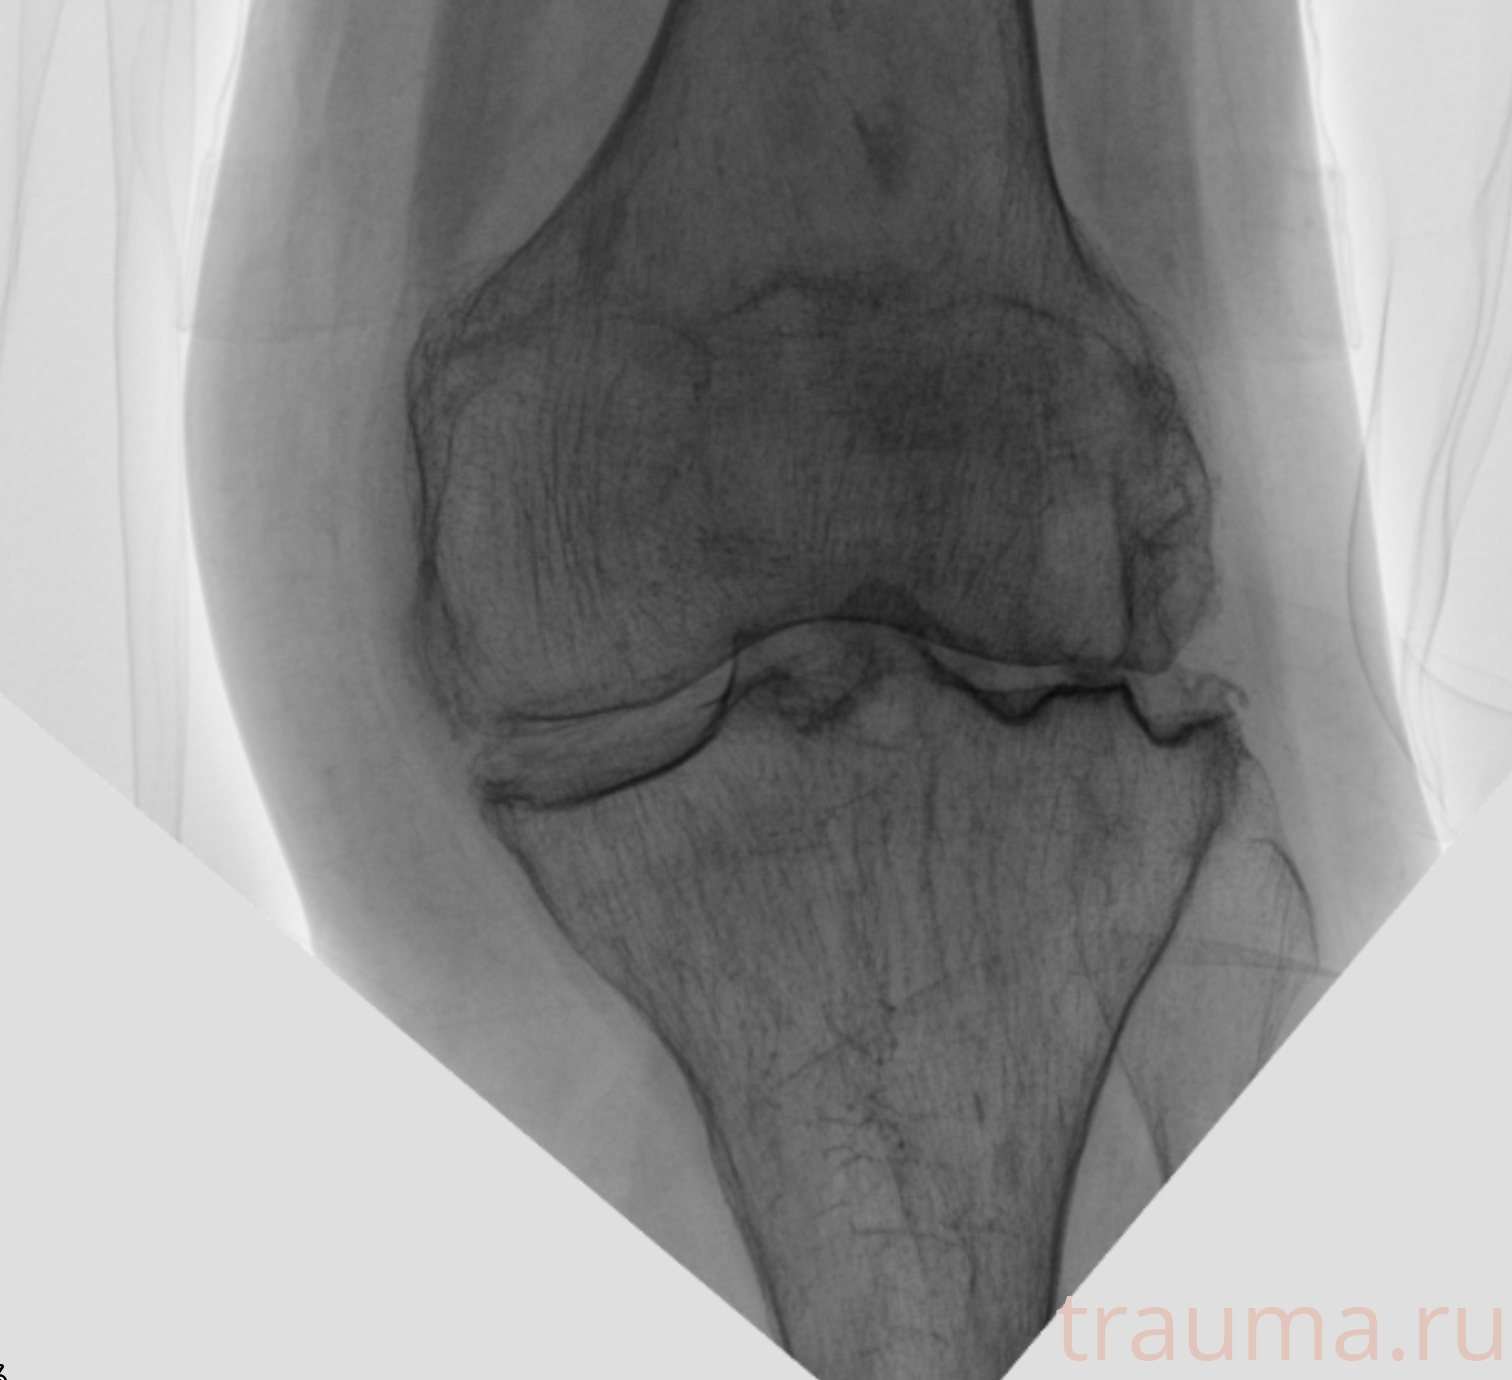

Рентген на дому: по вашему адресу приезжает врач-рентгенолог, травматолог-ортопед с мобильным рентгеновским аппаратом, проводит диагностику травмы или заболевания, делает необходимые рентгенограммы, дает рекомендации по дальнейшему лечению. Получить качественные снимки в домашних условиях возможно благодаря уникальной методике, разработанной МосРентген Центром для института  Склифосовского